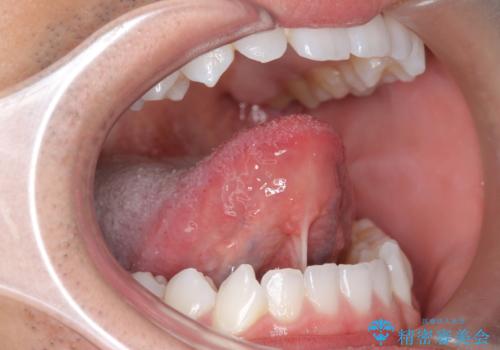

[ 舌小帯の形成 ] 滑舌が悪いと言われる、話しづらい

担当医 大元洋佑

![[ 舌小帯の形成 ] 滑舌が悪いと言われる、話しづらいの症例 治療前](https://seimitsushinbi.jp/wp/wp-content/uploads/2021/07/65efe28f05c8bc8266a054e337d8a987-500x350.jpg?v=1626308574)

![[ 舌小帯の形成 ] 滑舌が悪いと言われる、話しづらいの症例 治療後](https://seimitsushinbi.jp/wp/wp-content/uploads/2021/07/9a0e2d1f2bdecf6d77e84a94c98c2f5e-500x350.jpg?v=1626308612)